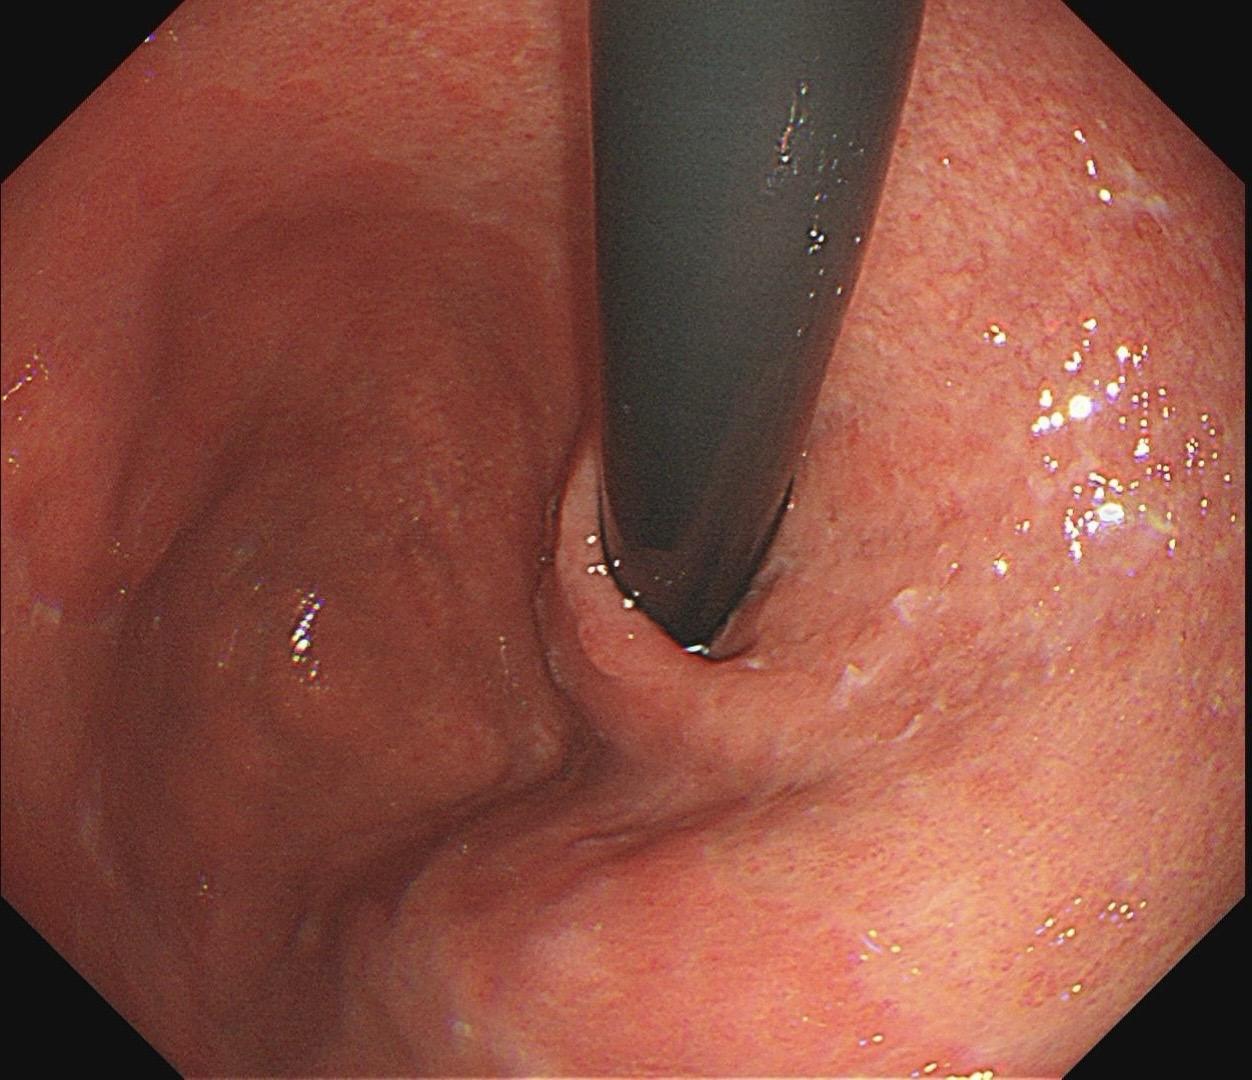

男,61岁,胃巨大褪色调病变。答案在最后一张图片,你猜对了吗? 患者因上腹部饱胀行胃镜检查,Hp阴性背景,胃窦至贲门下见一巨大褪色调病变,边界清晰,病变相对表浅,未见明显溃疡及隆起,胃壁较柔软,充气顺应性佳,予多点活检确诊,拟外科手术行全胃切除。做这么多年胃镜,还是第一次遇到这样的……